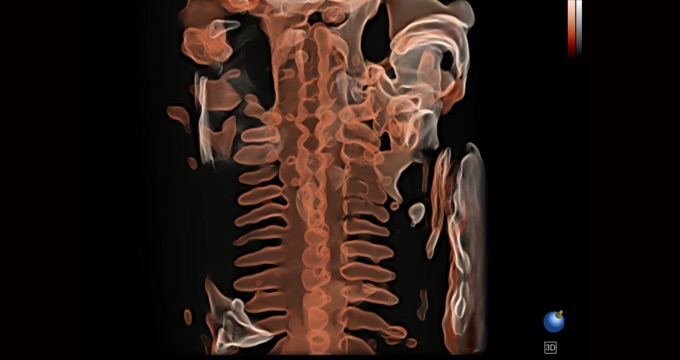

• S-Live Silhouette

A través de la aplicación de una fuente de luz virtual y un efecto de sombra, S-Live Silhouette ve a través de la superficie y delinea claramente los contornos de huesos, órganos, cavidades, paredes de los vasos y otras estructuras internas. Es una herramienta beneficiosa para identificar anatomía normal y diagnosticar malformaciones congénitas complejas.